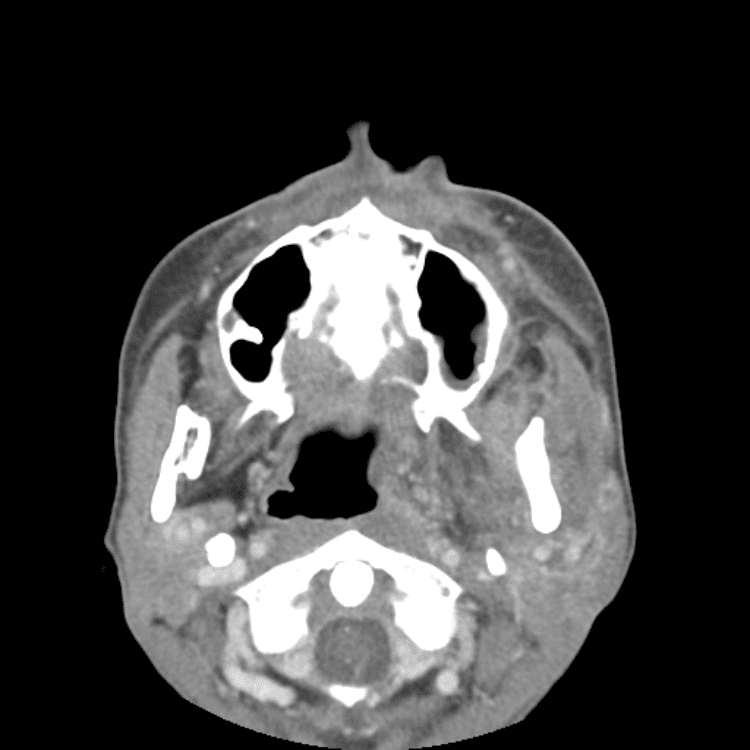

Head and Neck

Practice

Simulates call by including subtle or difficult cases and some normals.

27 cases